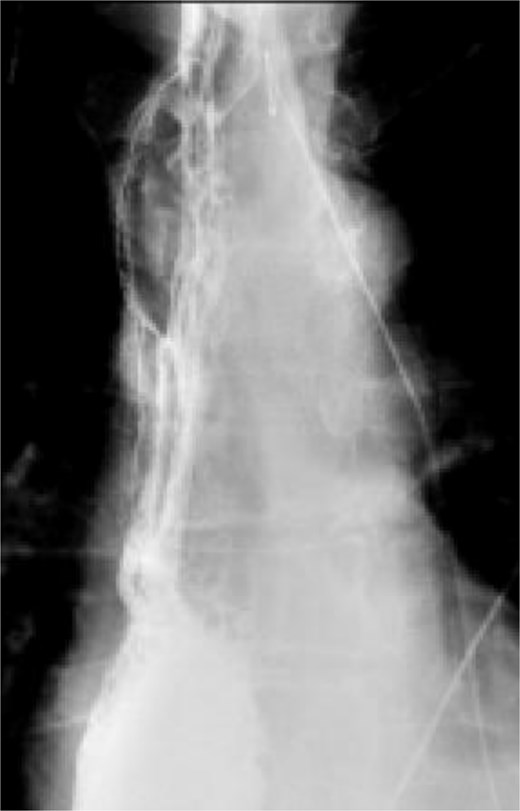

A multidisciplinary discussion was held and in the setting of the rapid tumor progression with biology favoring sarcoma and no evidence of distant disease, the decision was made to pursue upfront surgical resection rather than neoadjuvant therapy. The patient underwent a three field near total esophagectomy with an uneventful postoperative hospital course. A fluoroscopic esophagram was performed on postoperative day 6 without evidence of contrast extravasation (Fig. 4). The final pathology revealed an 8.7 cm high-grade pleomorphic rhabdomyosarcoma with mucosal and submucosal invasion, sparing the muscularis propria with 0/11 lymph node involvement (Fig. 5). This was formally graded as Stage IIIA (pT2N0M0), based on the soft tissue sarcoma criteria of AJCC.

Fluoroscopic esophagram showing an intact anastomosis without contrast extravasation on postoperative day 6 status post-esophagectomy.